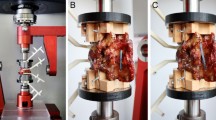

The study was approved by the responsible investigational review board. Fifteen spinal segments (TH12/L1: 3, L1/2: 3, L2/3: 3, L3/4: 3, L4/5: 3) originating from seven fresh frozen cadavers (Table 1; Science Care, Phoenix, AZ, USA) were tested. After thawing, CT scans (SOMATOM Edge Plus, Siemens Healthcare GmbH, Erlangen, Germany) were performed to exclude bony defects. The specimens were carefully dissected without harming bony processes, paraspinal ligaments or the intervertebral discs. After preparation, the segments were mounted on a testing machine (Fig. 4a) using custom 3D-printed-clamps [13].

Biomechanical experiments

Biomechanical testing of the 15 specimens was performed on a biaxial (linear & torsion) static testing machine (Zwick/ Roell Allroundline 10kN and testXpert III Software, ZwickRoell GmbH & Co. KG, Germany; Fig. 1a). The system is based on a traverse to generate vertical compression and tension and a torsion motor to generate torque in the horizontal plane. The machine was complemented with a testing setup consisting of an x–y-table and holding arms that allow for specimen fixation in a horizontal orientation for flexion–extension (FE), lateral shear (LS), lateral bending (LB), and anteroposterior shear (AS), and in a vertical orientation for axial rotation (AR). A customized mounting apparatus for the clamped specimens was used [13], consisting of high-precision fitting rings, pins, and a mechanism to compress the connection with a defined load before tightening. Loading was applied to the cranial vertebra while the caudal vertebra was fixed to the x–y-table allowing for translational movement orthogonal to the loading direction. Coupled motions around the x- and y-axis were prevented, restricting all motions to the test plane. With this configuration, translation forces, as might occur with a fully constrained setup, are eliminated, resulting in pure moments and pure forces in the plane of interest. Further details on the test setup, including images of all loading configurations, are provided in a previously published study [16].